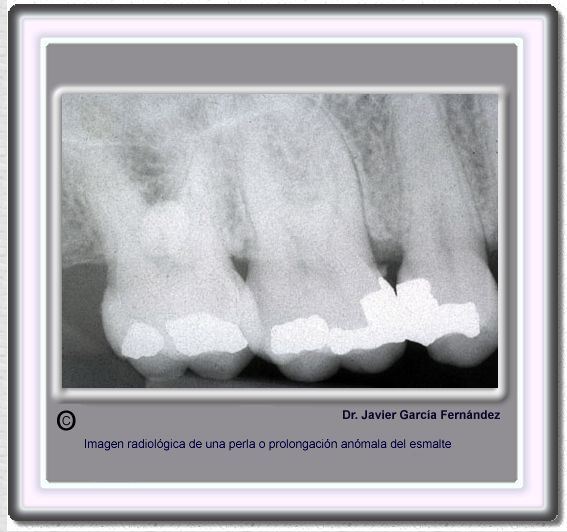

image432